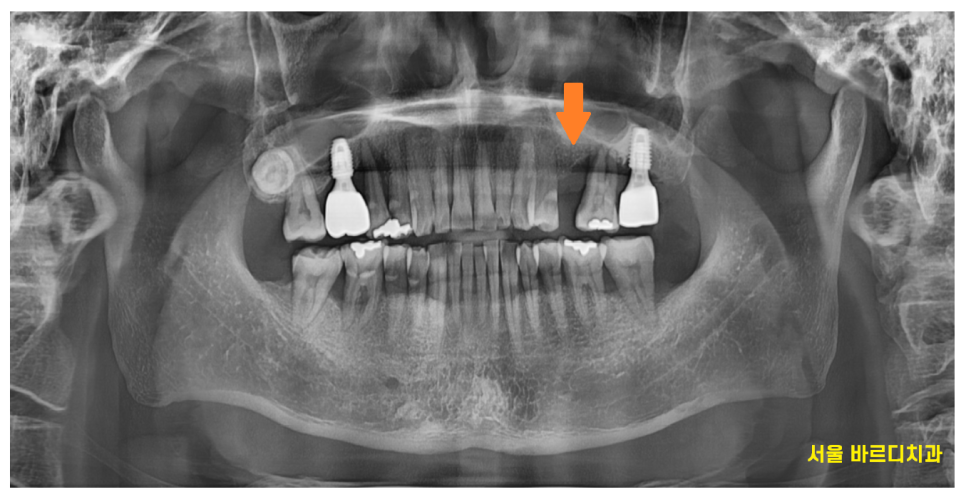

이미 이를 하나 뽑힌채로 오셨는데

치아가 없는 부위 옆에 치아도 좋지 않네요..

잇몸 내려감이 관찰

뽑은 부위는 동굴처럼 잇몸뼈가 푹 꺼졌습니다.

왼쪽 위에 먼저 임플란트 1개를 식립하였습니다.

240622

왼쪽 치료가 끝나고

식사를 할 수 있게 된 뒤

오른쪽 치료를 시작했습니다.